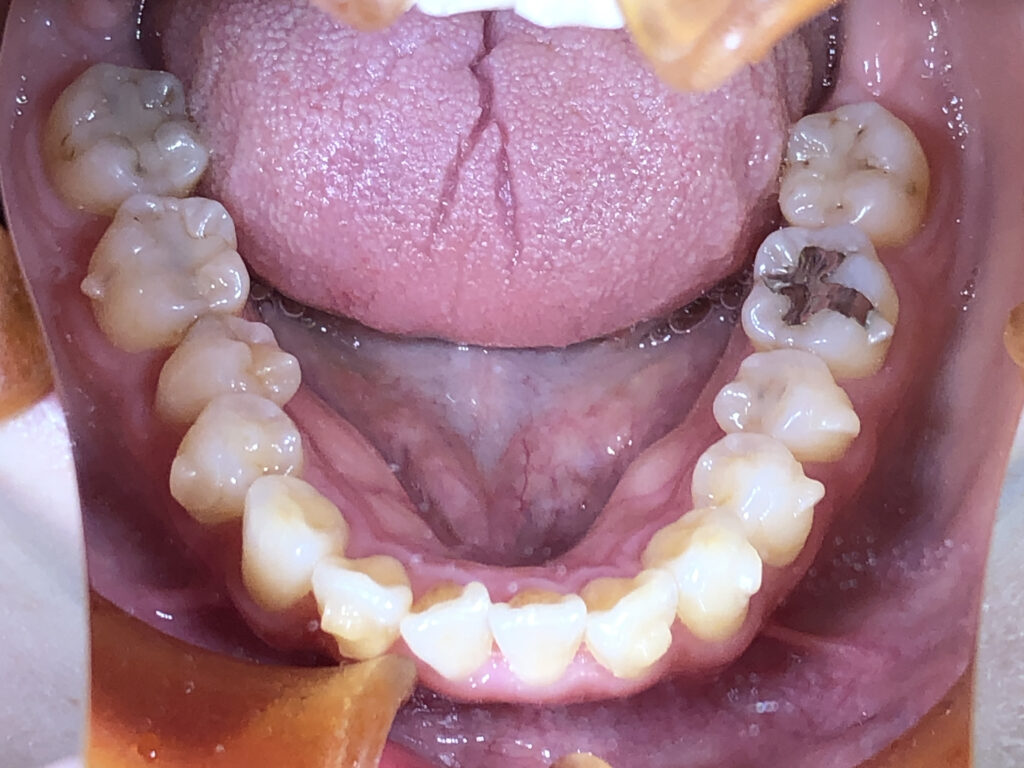

下顎

治療後

患者様は前歯の隙間と歯の向きを主訴として来院されました。前歯の隙間は審美面だけでなく、発音や食べ物の停滞にも影響しやすい状態でした。また、下顎前歯部に歯石が付きやすいことは、歯列不正により清掃不良部位が生じていることが一因と考えられました。 インビザライン矯正では、前歯の角度と位置を適切にコントロールし、隙間を閉じて調和のとれた歯列に整えました。同時に下顎前歯の叢生を改善することで、歯石の付着しやすい環境を改善し、将来的な歯周病リスクの低減にもつながる治療計画としました。下顎はもう少し改善可能と説明したところ、十分満足とのことで、治療終了としました。 |